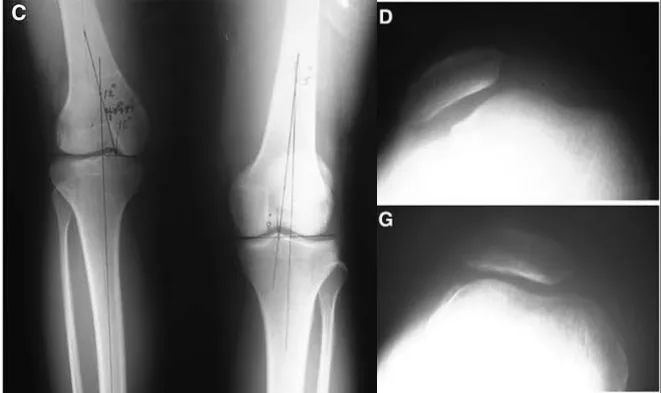

伊利扎洛夫骨延长技术。A.伊利扎洛夫骨延长法;B.在短缩骨干的上部做截骨;C.术后2周后,每天以1 mm距离牵拉延长截骨远端。

伊利扎洛夫的骨延长技术可以说实现了骨科「四维矫形」的完美理念,即三维外固定+时间变量(每天1 mm牵拉)。